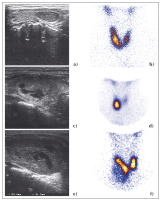

Abbildung 4a-f: Beispiele verschiedener Befunde bei Patienten mit Knotenstruma: Zur Beurteilung der Knoten sind sowohl die Sonographie als auch die Szintigraphie unerlässlich. Patient 1: Der rechts gelegene sonographisch echoarme, solide Knoten kommt szintigraphisch „warm“ zur Ansicht (a, b). Patient 2: Der sonographisch größtenteils echogleiche Knoten hat einen echoarmen Randsaum (Halo) und ist teilweise zystisch degeneriert. Szintigraphisch kommt er „heiß“ zur Ansicht, im restlichen Schilddrüsenparenchym ist die Aktivitätsbelegung vermindert: Unifokale funktionelle Autonomie (c, d). Patient 3: Der sonographisch fast den gesamten rechten Lappen einnehmende Knoten zeigt einzelne echoärmere Anteile und ist ebenfalls zystisch degeneriert. Er stellt sich szintigraphisch „kalt“ dar (e, f).

Keywords: AutonomieSchilddrüseSzintigraphie